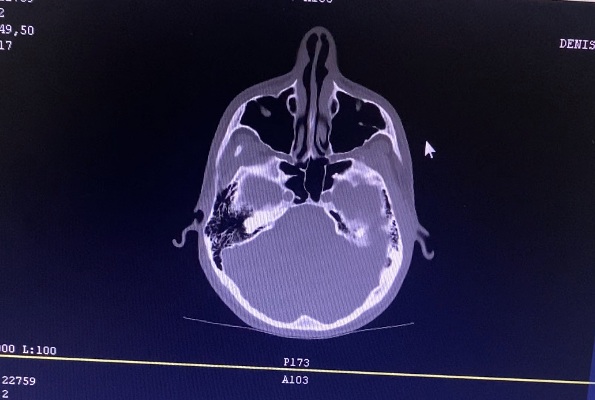

Пациенту было назначено соответствующее лечение, по окончании курса было сделано повторное КТ ППН (спустя 2,5 недели).

Снимки после курса лечения

По полученным результатам можно судить о санации пазух. На момент повторного осмотра пациент жалоб не предъявлял.